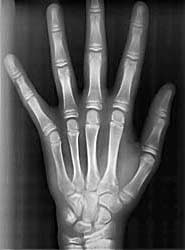

- Röntgenaufnahme der Hand (nicht immer)

Hier lässt sich der augenblickliche Wachstumsstand eines Jugendlichen feststellen. Kann eine Kieferveränderung noch durchgeführt werden?